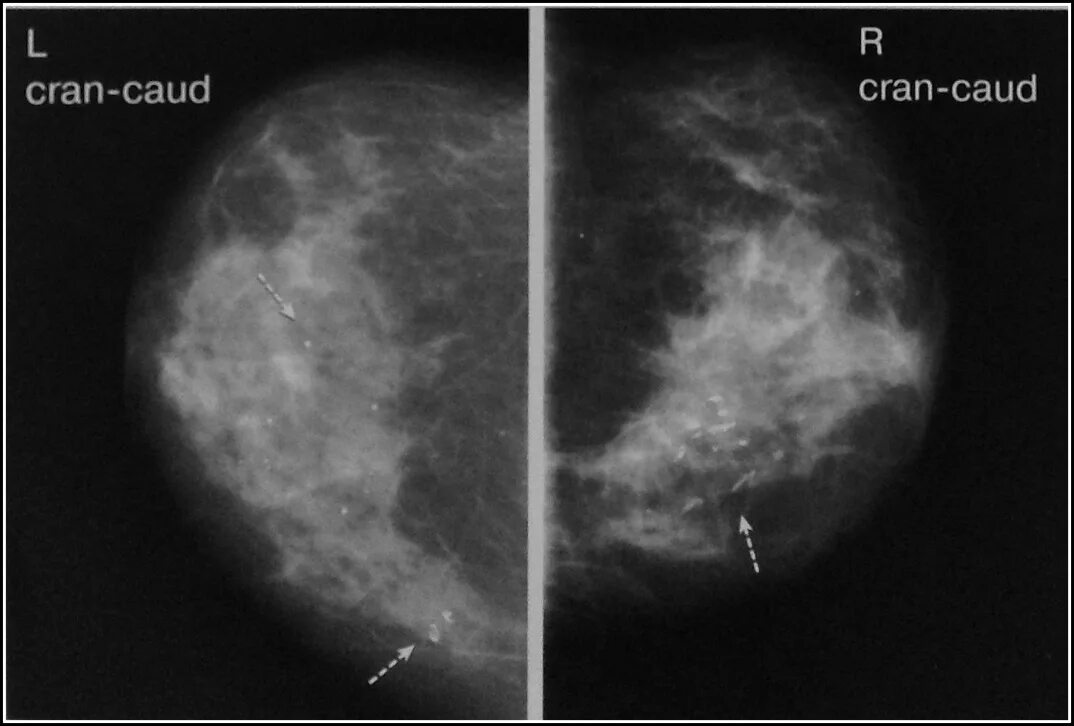

Опухолевидное образование молочной железы